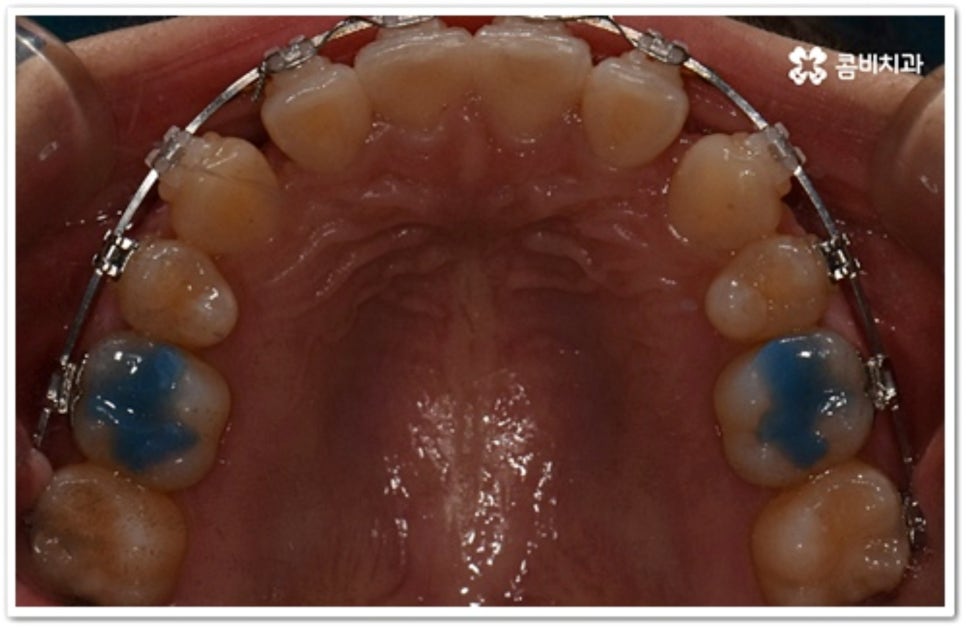

그러나 만약 덧니가 많고 부정 교합 정도가 심하거나 치아가 고르게 배열될 공간이 크게 부족하다면 덧니 발치 교정 치료를 진행하게 되는데, 이때 보통 치아 중에 기능이 가장 적은 소구치를 우선적으로 발치하게 되지만 (사진에서 확인할 수 있는 케이스) 환자분들의 상황에 따라 필요 없는 사랑니를 발치하고 어금니부터 뒤로 밀어 자리를 잡아주거나 충치 또는 짧아진 치근 등으로 심하게 손상된 치아가 있는 소구치를 우선적으로 발치하여 교정 치료를 진행하기도 하고, 필요시 임플란트와 병행하여 치료를 진행하는 경우도 있습니다. 따라서 먼저 자신의 상황에 대해서 면밀하게 검진을 받아보고 자세한 치료 계획에 대해서 의료진과 충분하게 상담해 보시는 게 좋을 거예요.

치아는 제자리로 돌아가려는 성질을 가지고 있어서 덧니 발치 교정이 끝난 후 일정 기간 동안은 유지 장치를 착용하여 이를 예방하고 정기 검진을 꼬박꼬박 받으면서 사후 관리를 철저하게 해 주는 게 좋을 거예요. 유지장치에는 고정식과 가철식이 있는데 치아 안쪽에 얇은 철사를 붙이는 고정식 (사진에서 볼 수 있는 사례) 은 앞니가 틀어지는 것을 방지해 주고, 뺐다 꼈다 하는 가철식은 교정 치료할 때 악궁 확장을 한 경우 전체 치열을 유지하기 위해 필요한 방식이라고 할 수 있어요. 환자분들 각각의 치료 과정이나 구강 상태에 따라 둘 중 하나를 선택하거나 두 가지 다 해야 하는 경우가 생길 수 있습니다.